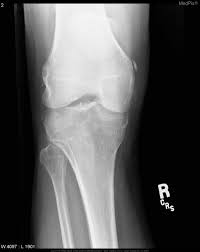

Pellegrini stieda syndrome is a medical problem which is characterized by pain, swelling and inflammation in the knee. It is a common incidental finding on knee radiographs. Pain and restriction of movements. The cause of the knee effusion is unknown. There is a moderately large knee effusion. The diagnosis pellegrini stieda disease was made. Is the presence of a radiological finding of calcification on the medial side of the knee as a consequence. It is likely that this patient has been an active sportsman in the past.

Pain and restriction of movements. The cause of the knee effusion is unknown. It is likely that this patient has been an active sportsman in the past. #foamed #foamrad #radiology #rad #elearnrad #voxelz #varunbabu #drbabu. Pellegrini stieda syndrome is a medical problem which is characterized by pain, swelling and inflammation in the knee. Most of the cases of pellegrini stieda lesions are not symptomatic, and pellegrini stieda syndrome is said to exist when the lesion becomes symptomatic i.e. Ayurvedic treatment is the natural way to treat pellegrini stieda syndrome. Is the presence of a radiological finding of calcification on the medial side of the knee as a consequence. The diagnosis pellegrini stieda disease was made. It is a common incidental finding on knee radiographs. With the ayurvedic treatment, it is possible to avoid surgery. This occurs due to the deposition of calcium on the inner side of the knee. Learn about this soft tissue calcification around the knee joint.

Pellegrini stieda syndrome is a medical problem which is characterized by pain, swelling and inflammation in the knee. The diagnosis pellegrini stieda disease was made. Learn about this soft tissue calcification around the knee joint. The cause of the knee effusion is unknown. There is a moderately large knee effusion. Pain and restriction of movements. Is the presence of a radiological finding of calcification on the medial side of the knee as a consequence. It is a common incidental finding on knee radiographs. Most of the cases of pellegrini stieda lesions are not symptomatic, and pellegrini stieda syndrome is said to exist when the lesion becomes symptomatic i.e. #foamed #foamrad #radiology #rad #elearnrad #voxelz #varunbabu #drbabu. It is likely that this patient has been an active sportsman in the past. There is evidence of osteoarthritis. This occurs due to the deposition of calcium on the inner side of the knee.